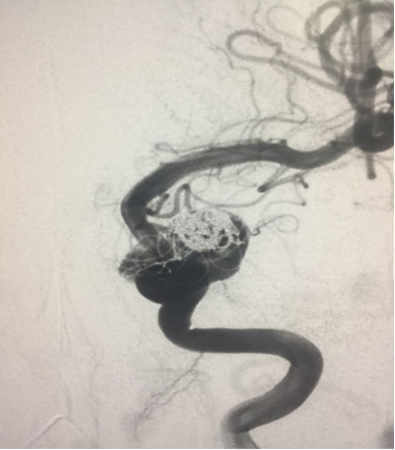

动脉造影早期可见流入道及流出道

造影剂有滞留

正位片晚期,希望半年后复查有个好结果